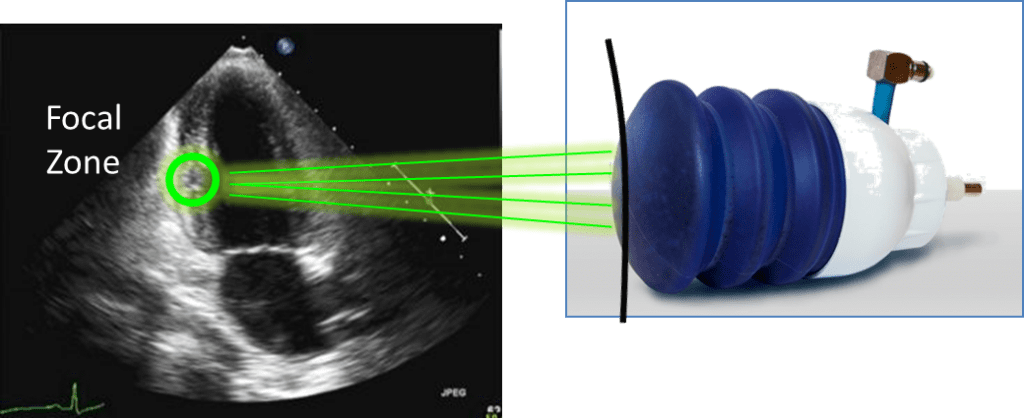

Principle

Low-energy focused shock waves (energy density 0.09 mJ/mm2)

Focused and controlled by echocardiography

Released by ECG trigger (during the refractory phase of the cardiac cycle)

The treatment is performed using a shock wave generator that is designed to address the unique clinical-anatomical requirements of the chest cavity. A cardiac ultrasound imaging system is used to locate the treatment area and to map the exact position and extent of the ischemic zone. Shock waves are then delivered via the anatomicalacoustic window to the treatment area under E.C.G. R-wave gating. Several treatment sessions are required to obtain optimal results.